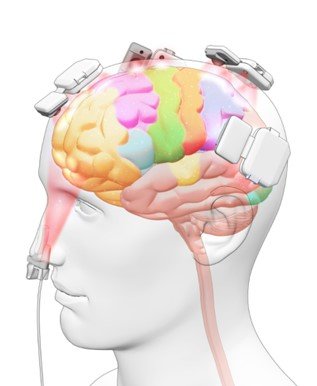

Figure 1. Penetration of NIR energy into a human cadaver using the Vielight Neuro.

Das Vielight Neuro ist für eine maximale Übertragung der Lichtenergie ausgelegt.

Das Headset der Neuro hat einen angeborenen Designvorteil, da die LED-Module der Neuro so konzipiert wurden, dass sie den Kontakt mit der Kopfhaut maximieren. Die mikrochip-gesteuerten LED-Module kontrollieren auch die Wärmeleistung,

Außerdem ist das Neuro-Headset so konzipiert, dass es sich an verschiedene Kopfgrößen und -formen anpassen lässt. Komfort und Effektivität für Ihr wichtigstes Organ – Ihr Gehirn.

Wir haben die Nase wegen ihrer Lage und Struktur ausgewählt. Die Nase ist ein Einfallstor für die 810nm-Lichtenergie im nahen Infrarot (NIR), um den ventralen Bereich (Unterseite) des Gehirns zu erreichen, der sonst unzugänglich wäre. Die Regionen des Gehirns, die sich auf der Unterseite des Gehirns befinden, spielen eine wichtige Rolle bei emotionalen Reaktionen, Entscheidungsfindung und Selbstkontrolle. Darüber hinaus ist der nasale (olfaktorische) Bereich direkt mit der Gedächtnisverarbeitung (Hippocampus, entorhinaler Kortex) und der Emotionssteuerung (Amygdala) verbunden und ermöglicht den Zugang zu anderen Bereichen des Gehirns (Thalamus).